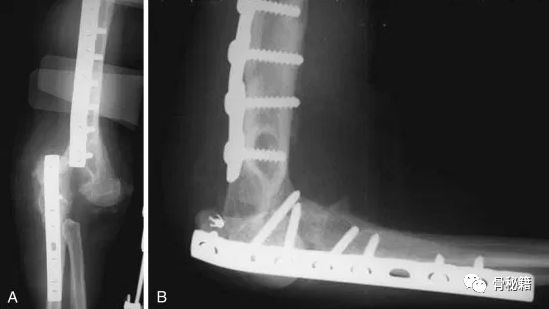

看看这些失败的case,肱骨远端不简单!

最难的最难的。。。灾难级的!当开放骨折+大量骨缺损遇到了感染你会怎么办?

30岁年轻男性

病例的结局

一期行外固定架+抗生素骨水泥控制感染,这个是常规的。

下一步?

二期同种异体肘关节移植术!并且将三头肌支点与原肘进行了重建

术后18个月,出现了失败和关节的不稳,但宿主和自体骨较好的结合了。

又进行了第二次肘移植,最后终于愈合